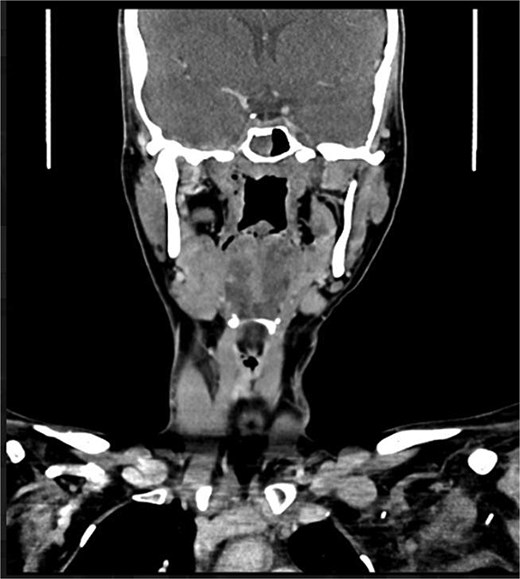

A 22-year-old female presented with progressive swelling in the left anterior chest wall above the left breast, associated with needle-like chest pain, left upper limb tingling, and weakness. The patient had a history of childhood cystic hygroma in the left axilla, previously excised. She denied constitutional symptoms but reported compressive symptoms such as shortness of breath, dysphagia, and hoarseness. A family history of breast cancer with thyroid metastasis was noted in her mother. On examination, the patient exhibited multiple bilateral solitary thyroid nodules and a bulky swelling in the left anterior chest and axilla. Computed tomography (CT) imaging (Fig. 1) revealed hypodense bilateral thyroid nodules, with magnetic resonance imaging (MRI) (Fig. 2) showing an enhancing left axillary lesion (2 cm, previously 1 cm) and an anterior chest wall lesion (1 cm). The mass, measuring 23 × 8 cm, extended to the lower left neck, left chest wall, and left axilla, encasing the neurovascular bundle without muscle or osseous invasion (Fig. 3). Fine-needle aspiration (FNA) cytology (Fig. 4) of the right thyroid nodule indicated atypia of undetermined significance (Bethesda III), while left-sided nodules and biopsies from the axilla, breast, and neck confirmed benign mature adipose tissue. The patient underwent total thyroidectomy, level V left neck exploration, and excision of lipomatous masses from the axilla, anterior chest, and breast, involving multiple surgical teams. Intraoperatively, vocal cords were preserved, and clear planes for lipoma excision were identified. The total excised lipomatous tissue weighed 13.57 kg (Fig. 5). Pathological examination confirmed mature adipose proliferation with no malignancy. Fluorescence in situ hybridization (FISH) ruled out MDM2 amplification, and genetic testing returned negative. Postoperatively, the patient developed deep vein thrombosis (DVT) in the left upper limb, diagnosed via Doppler study, and was treated with low-molecular-weight heparin (LMWH) followed by rivaroxaban. Follow-up MRI at 2 days and 3 months confirmed no residual or recurrent tissue growth. The patient started levothyroxine for thyroid function management and monitored for optimal dosing.

Interval increase in size of the large left upper lateral cervical, sub-pectoral, and axillary region fatty lesion protruding beyond the pectoralis major muscle into the upper breast region, keeping with lipomatosis.

Left chest wall lipomatosis with extension to the left neck and left axilla with thin septations, and there is a small enhancing focus (within the fatty lesion) which could be a small enhancing nodule or lymph node. The overall measurement has relatively increased (consider patient maturation).

Partially scanned left thoracic lipomatosis extending to the lower neck with mild mass effect over the left internal jugular vein. A multilocular goiter with a complex thyroid nodule is noted in the lower neck.